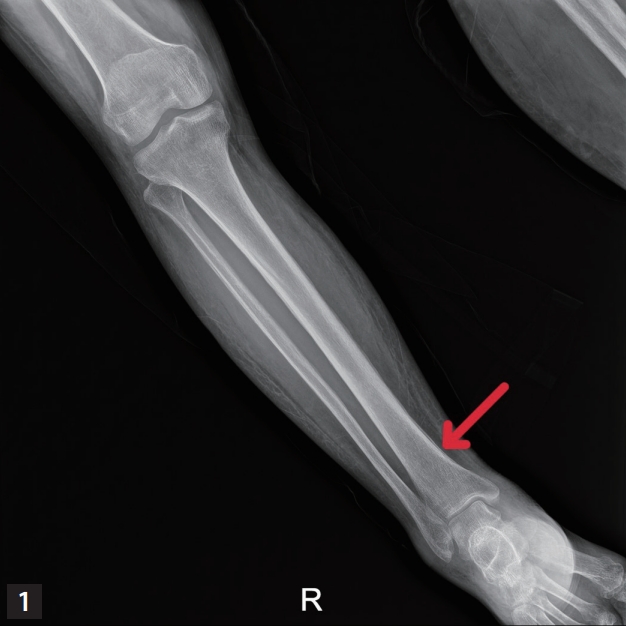

A 58-year-old female was admitted to a hospital for progressive both leg pain and swelling for 1 month. She has a history of myelofibrosis, transformed into acute myeloid leukemia, and received allogeneic hematopoietic stem cell transplantation (HSCT) 2 months ago. One month after HSCT, she was diagnosed as probable invasive pulmonary aspergillosis and received oral voriconazole. After 1 month of voriconazole therapy, she was admitted for progressive swelling and tenderness on both foot and ankle (around malleolus). Absolute neutrophil count was 2,000 u/L (reference value 2,500–7,000 u/L). The blood level of C-reactive protein was 13.6 mg/dL (reference value 0–0.6 mg/dL), creatine kinase 11 U/L (reference value 25–200 U/L), and alkaline phosphatase 351 IU/L (reference value 44–147 IU/L). Empirical cefazolin for possible cellulitis showed no improvement. Bilateral lower leg X-ray showed diffuse thin linear periosteal reaction in both tibia and fibula and diffuse soft tissue swelling in both lower legs (Fig. 1). Magnetic resonance imaging (MRI) of bilateral lower leg revealed diffuse high signal intensity and enhancement along the periosteum of tibia and fibula (Fig. 2).

Voriconazole contains three fluoride atoms, when compared to posaconazole and fluconazole which contain two [1-3]. The previous study showed that voriconazole develops hyper-fluorosis, potentially associated with periostitis, whereas other azoles such as fluconazole and posaconazole has lower risk for this condition [4] The most common symptom for voriconazole-associated periostitis is localized diffuse bone pain [5-8]. Radiographs show periosteal reaction, periosteal bone formation and periosteal thickening [8]. Computed tomography reveals periosteal reaction and exostoses [9]. MRI showed thick and irregular periosteal edema along the outer cortical surfaces of the bilateral proximal femoral shafts indicative of periostitis [9-11]. Symptoms usually resolves after discontinuation of voriconazole.